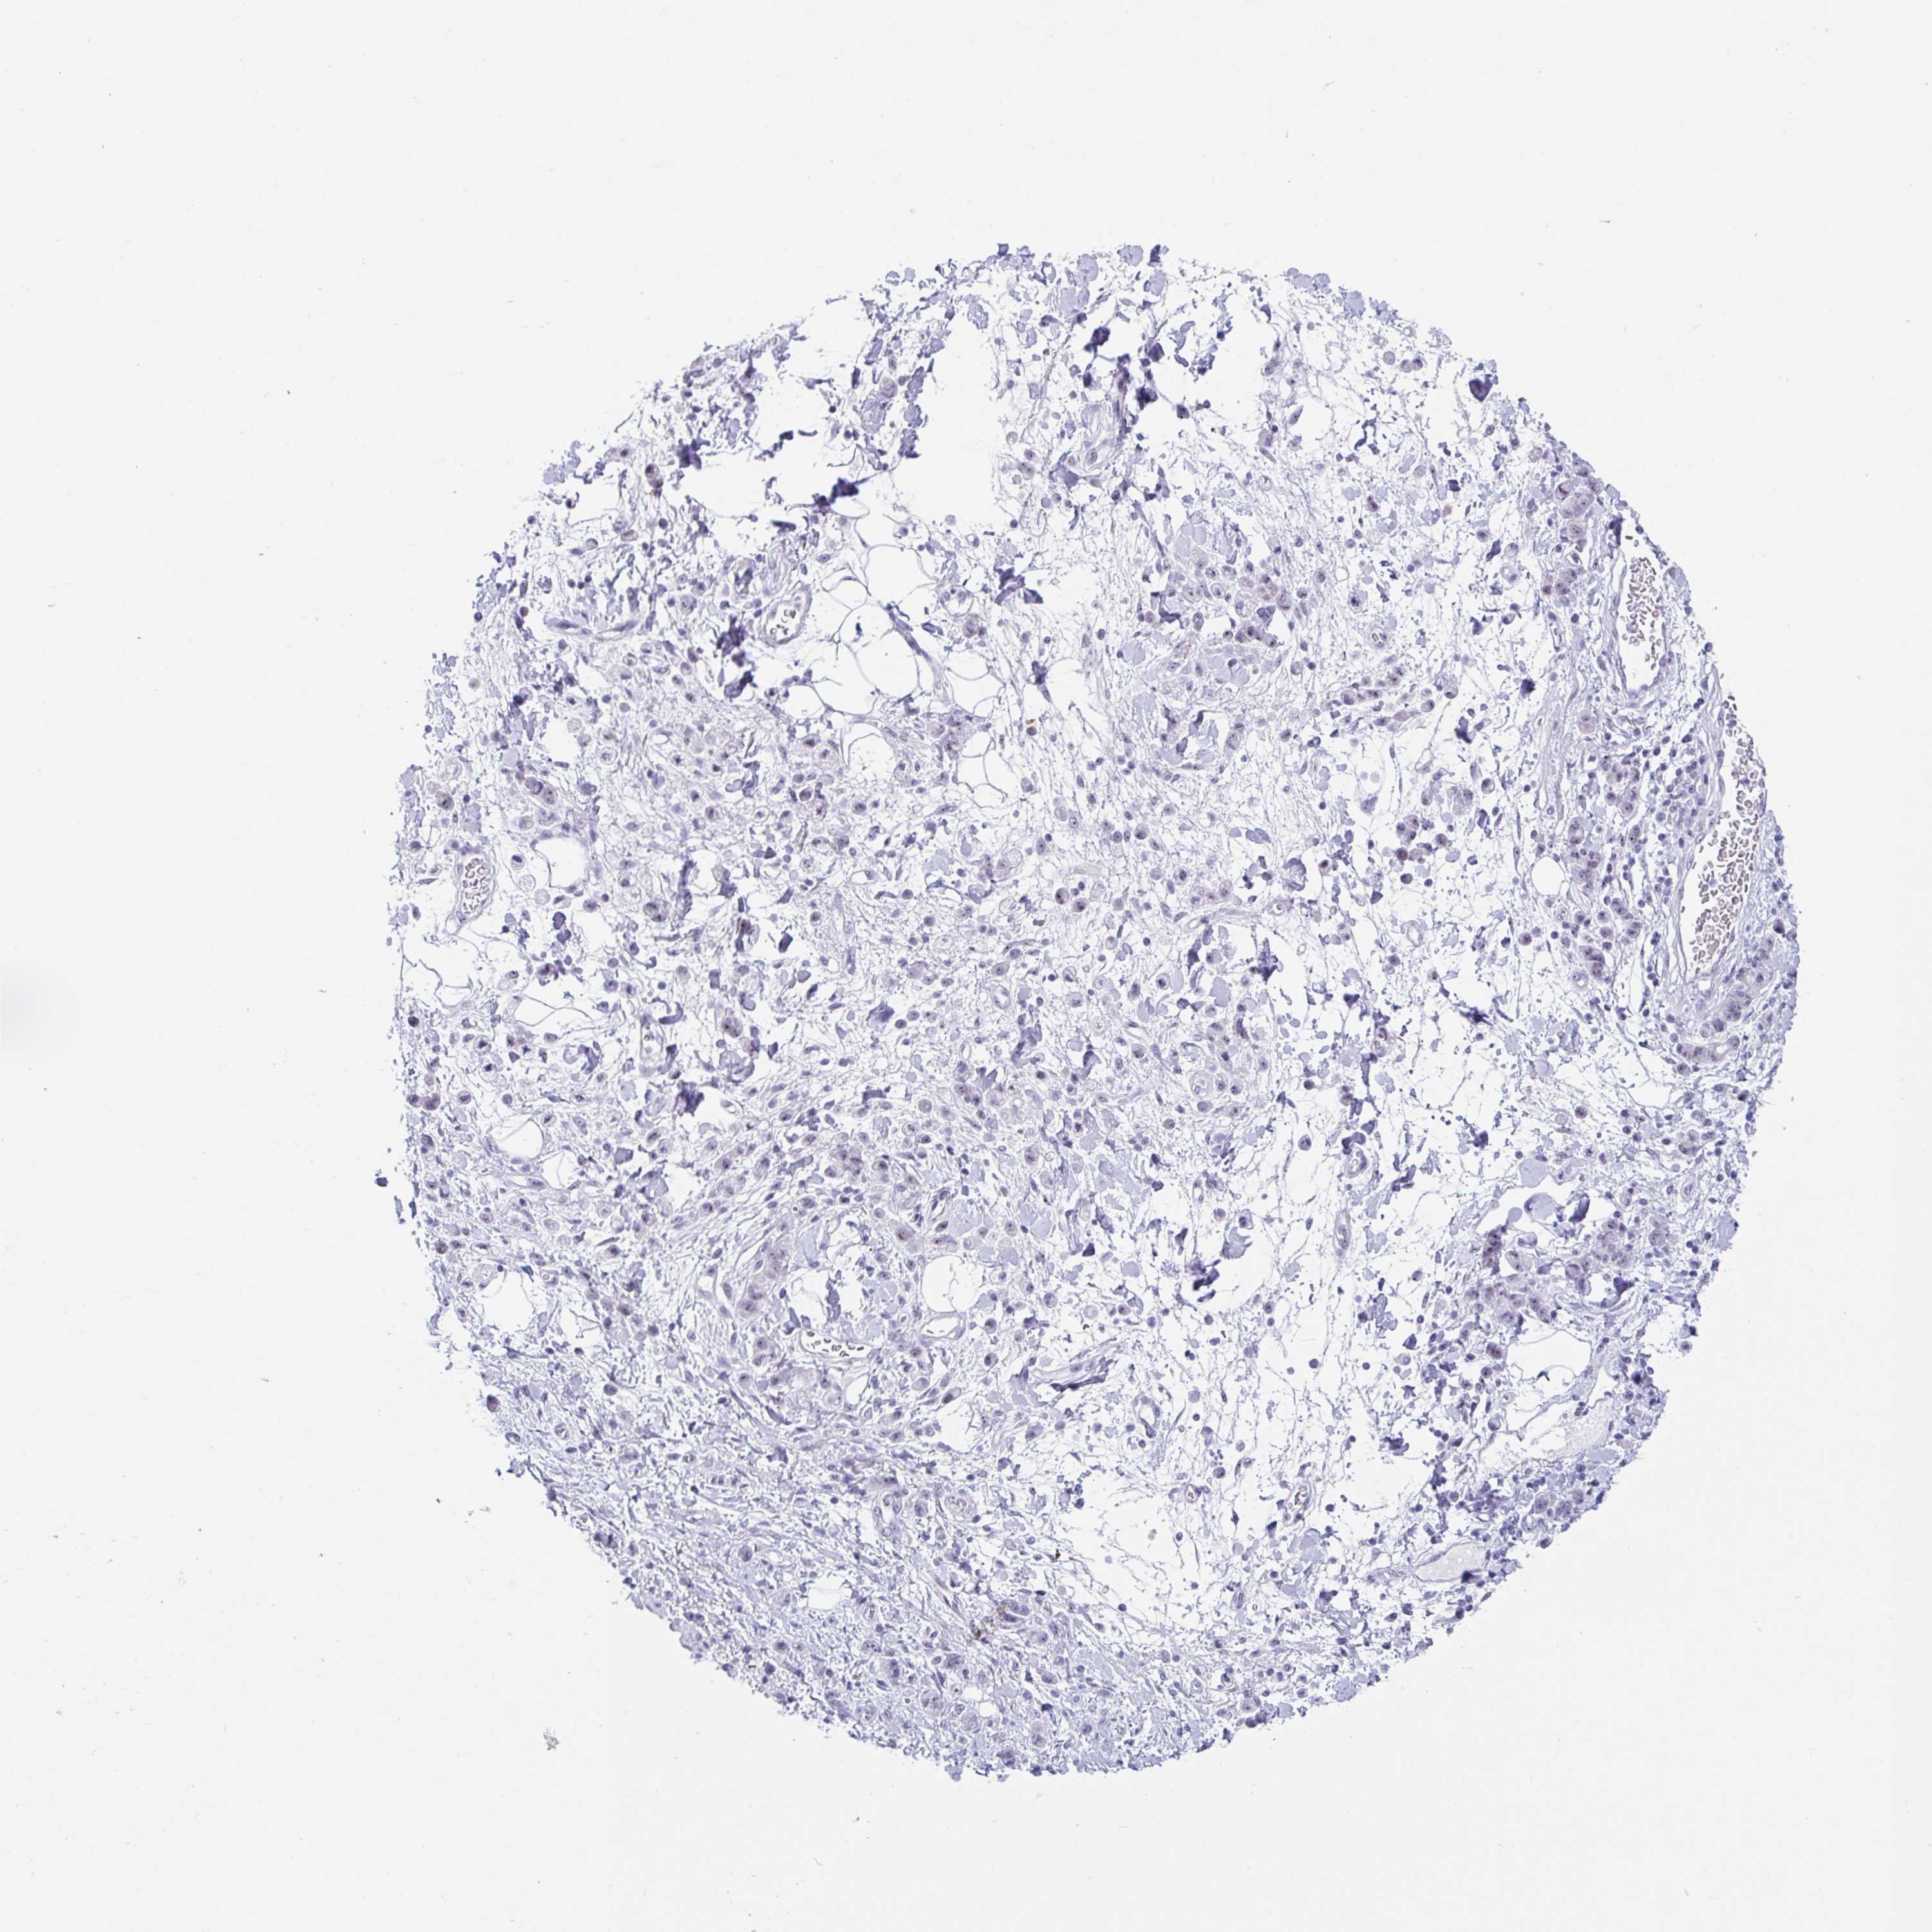

STOMACH CANCER - Protein expressioni

A mouse-over function shows sample information and annotation data. Click on an image to view it in a full screen mode. Samples can be filtered based on level of antibody staining by selecting one or several of the following categories: high, medium, low and not detected. The assay and annotation is described here.

Antibody stainingi

Antibody staining in the annotated cell types in the current human tissue is reported as not detected, low, medium, or high, based on conventional immunohistochemistry profiling in selected tissues. This score is based on the combination of the staining intensity and fraction of stained cells.

Each image is clickable and will lead to virtual microscopy that enables deeper exploration of all samples and also displays staining intensity scores, fraction scores and subcellular localization as well as patient and tissue information for each sample.

Antibody HPA051671

Antibody HPA053556

Staining

High

Medium

Low

Not detected

Intensity

Strong

Moderate

Weak

Negative

Quantity

>75%

75%-25%

<25%

None

Location

Nuclear

Cytoplasmic/membranous

Cytoplasmic/membranous,nuclear

Adenocarcinoma, NOS